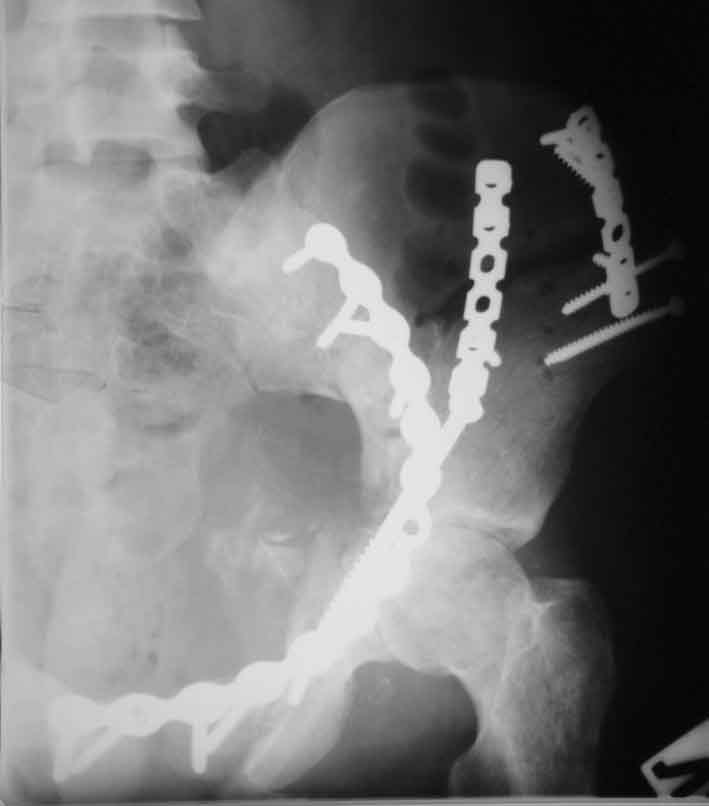

Рентгенограммы после операции

подвздошная

A>РО - картина не очень, есть видимость винтов во впадине

По всей видимости, вы имеете в виду канюлированный винт, который проецируется на вертлужной впадине. Та вот, он проведен не через лонную, а седалищную кость. Вертлужная впадина абсолютно интактна. Это хорошо видно на проекции inlet.